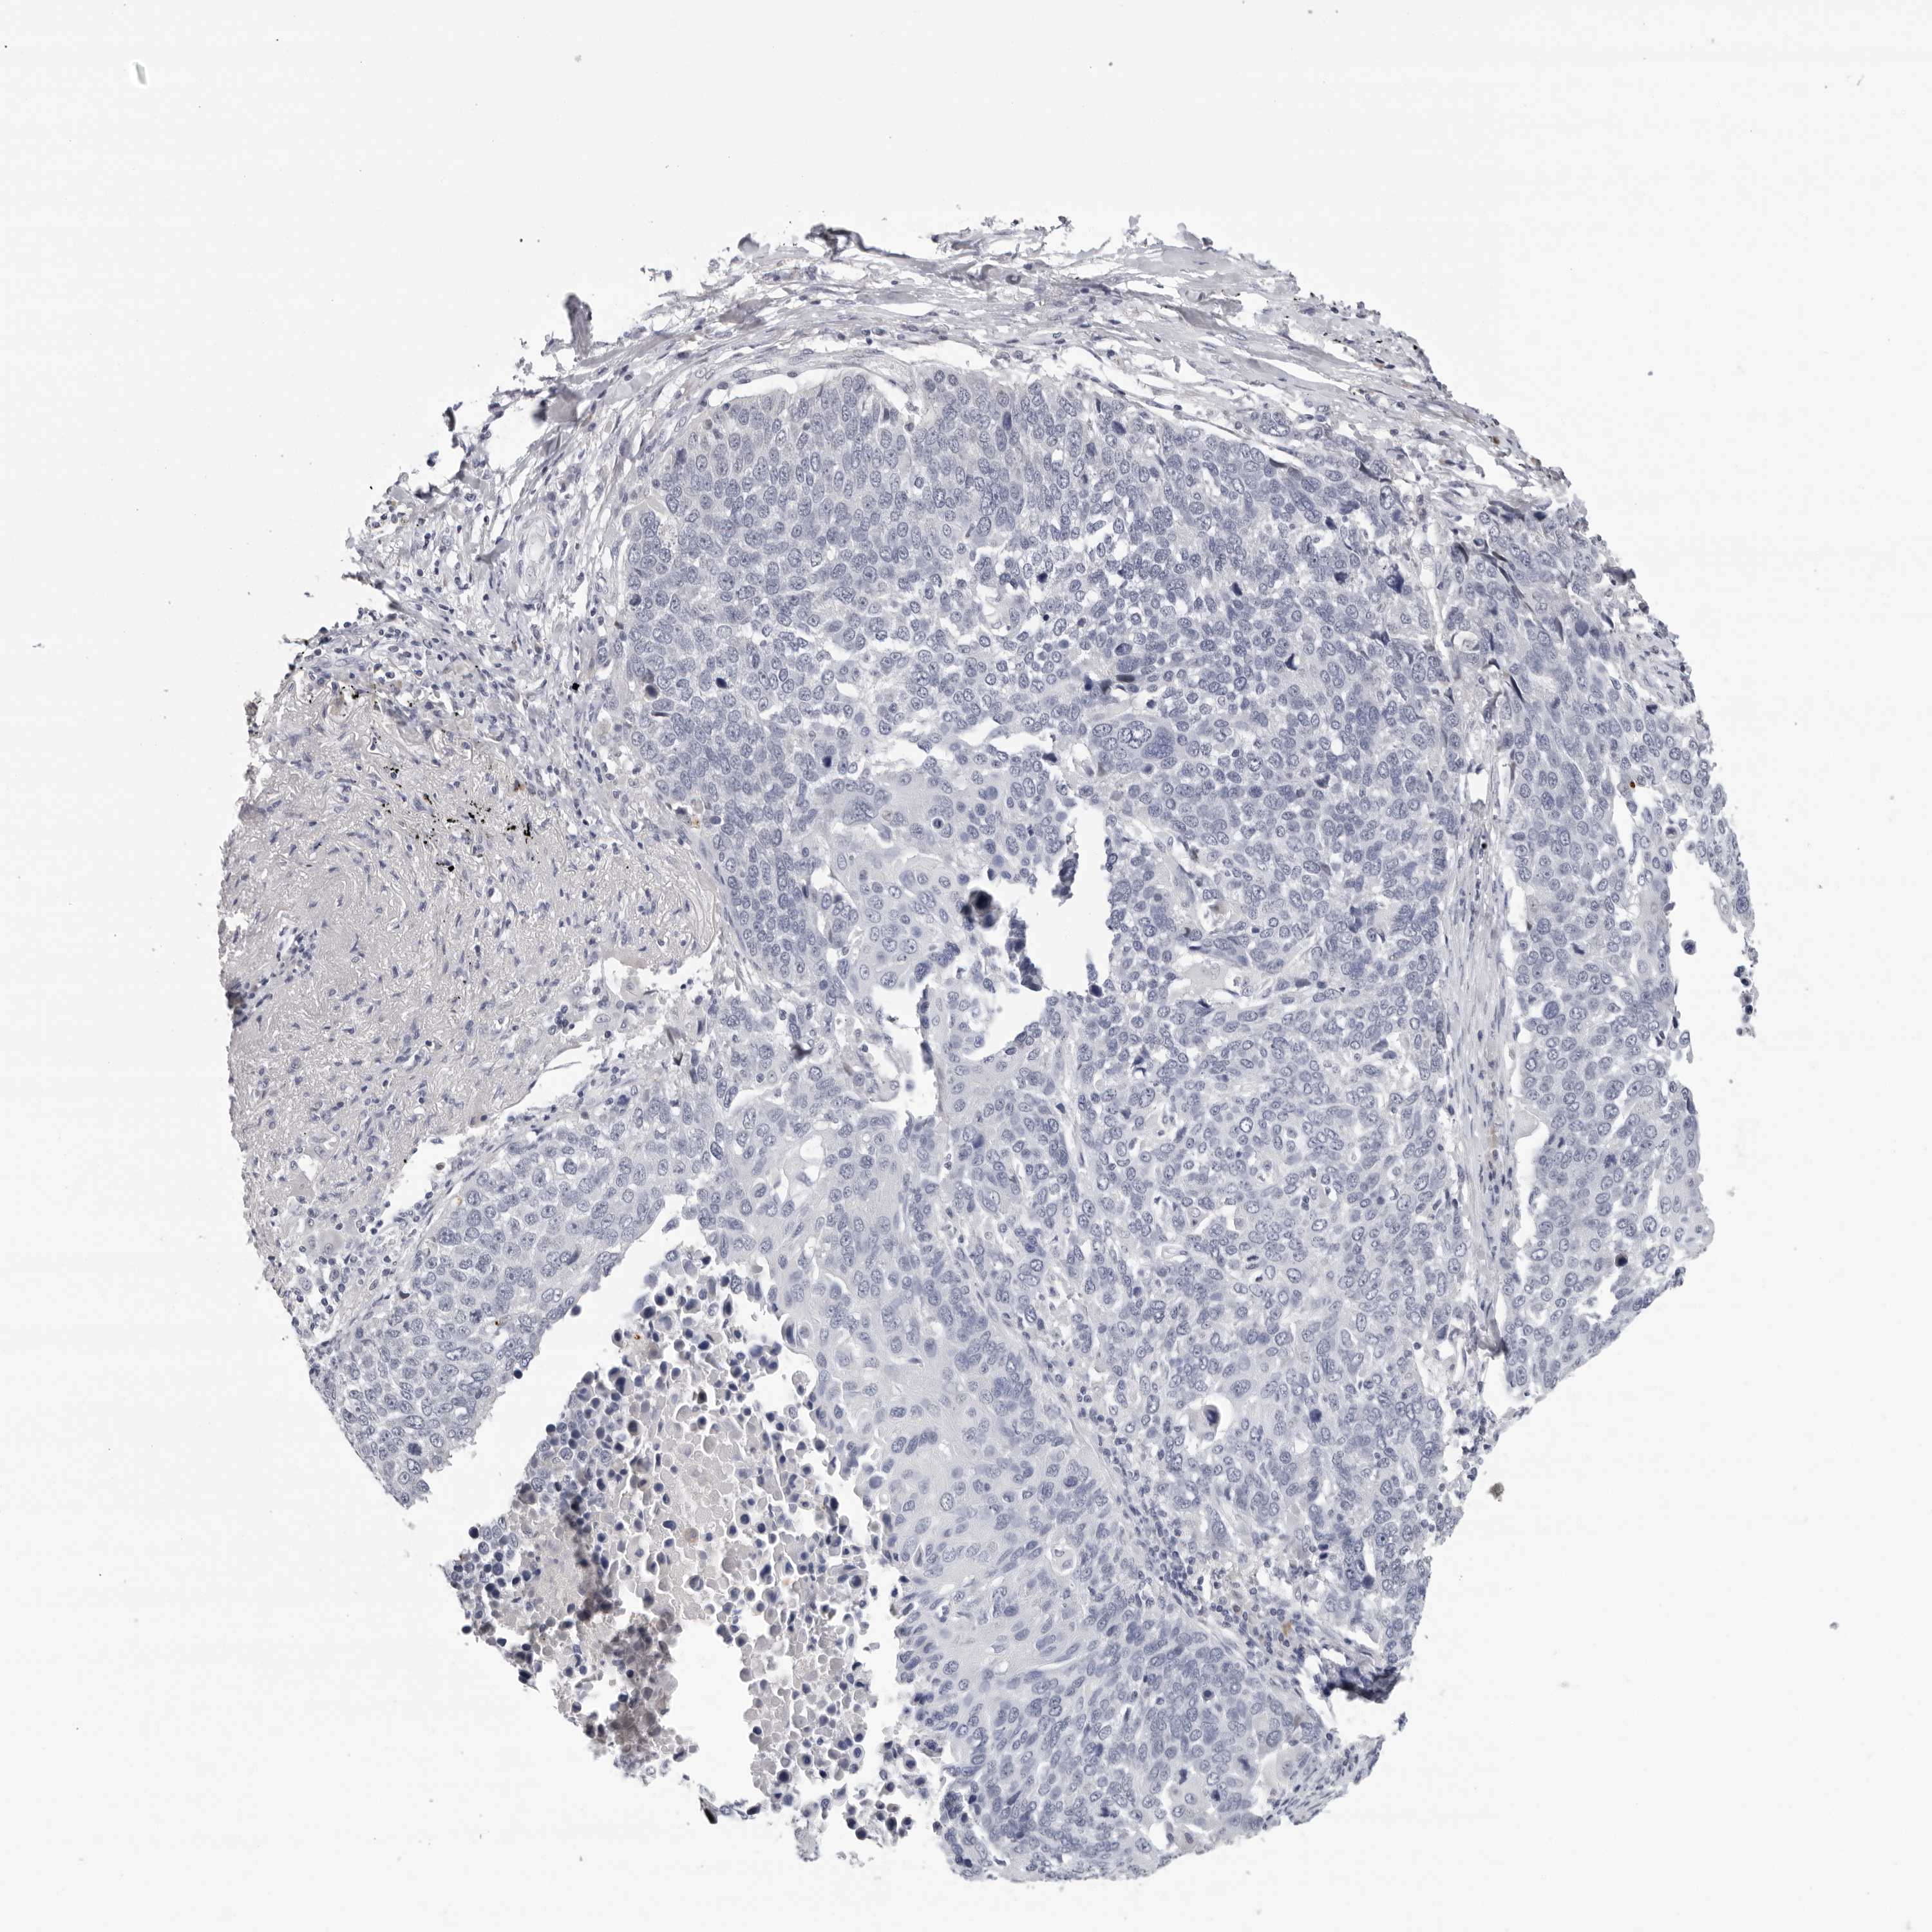

LUNG ADENOCARCINOMA (TCGA) - Interactive survival scatter ploti

The Survival Scatter plot shows the clinical status (i.e. dead or alive) for all individuals in the patient cohort, based on the same data that underlies the corresponding Kaplan-Meier plots. Patients that are alive at last time for follow-up are shown in blue and patients who have died during the study are shown in red.

The x-axis shows the expression levels (FPKM) of the investigated gene in the tumor tissue at the time of diagnosis. The y-axis shows the follow-up time after diagnosis (years). Both axes are complimented with kernel density curves demonstrating the data density over the axes. The top density plot shows the expression levels (FPKM) distribution among dead (red) and alive patients (blue). The right density plot shows the data density of the survived years of dead patients with high and low expression levels respectively, stratified using the cutoff indicated by the vertical dashed line through the Survival Scatter plot. This cutoff is automatically defined based on the FPKM cutoff that minimizes the p-score. The cutoff can be changed by dragging the vertical line or by entering a cutoff value in the square labeled "Current cut-off".

Under the Survival Scatter plot the p-score landscape (black curve; left axis) is shown together with dead median separation (red curve; right axis). Dead median separation is the difference in median mRNA expression between patients who have died with high and low expression, respectively. It is calculated as follows: median FPKM expression of dead patients with high expression - median FPKM expression of dead patients with low expression. This is intended to aid the user in visually exploring custom cutoffs and the associated p-scores and dead median separation.

Individual patient data is displayed and can be filtered by clicking on one or more of the category buttons on the top of the page. Categories describing expression level and patient information include: high, low, alive, dead, female, male and tumor stages. The scale of the x-axis can be toggled between linear and log-scale by clicking on the "x log" button. Mouse-over function shows TCGA ID, patient information and mRNA expression (FPKM) for each patient.

& Survival analysisi

Kaplan-Meier plots summarize results from analysis of correlation between mRNA expression level and patient survival. Patients were divided based on level of expression into one of the two groups "low" (under cut off) or "high" (over cut off). X-axis shows time for survival (years) and y-axis shows the probability of survival, where 1.0 corresponds to 100 percent.

ZNF502 is potential prognostic, high expression is favorable in Lung Adenocarcinoma (TCGA)

: 0.87

Average pTPM 1.1

Number of samples 497